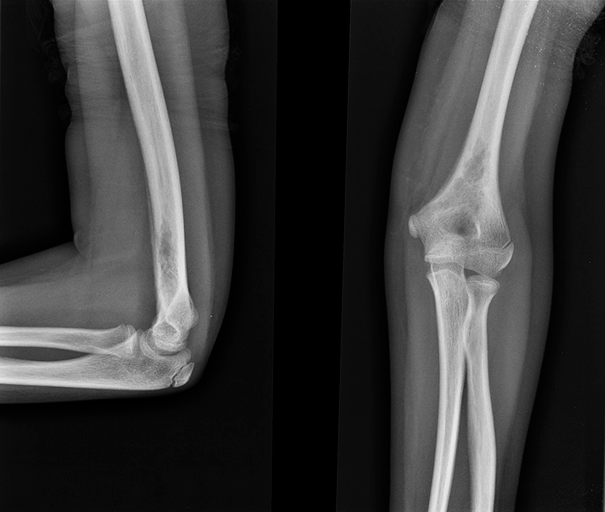

Рисунок 3. Эозинофильная гранулема костей черепа (рентгенограмма)

https://radiopaedia.org/cases/eosinophilic-granuloma-1